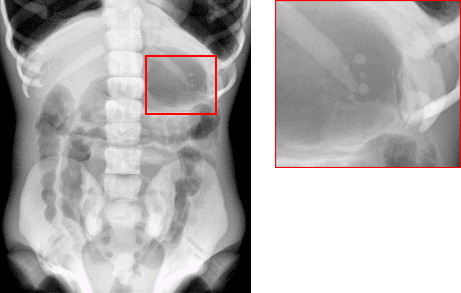

Knee / Weight bearing - Human knee

Chest - Lungman Phantom

Before

After

4343 + Linear Motion: Lungman

4360(대면적): Lungman